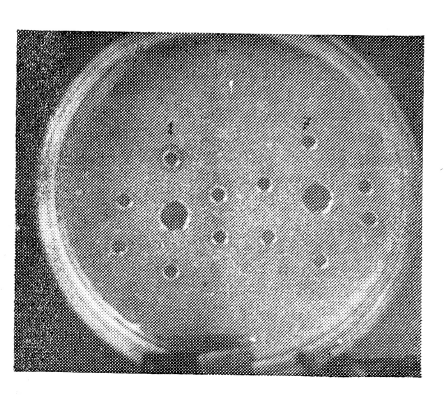

II тип пленок позволяет рассчитать плазминовую активность, обусловленную взаимодействием внутренних активаторов плазминогена исследуемого субстрата. При этом создаются оптимальные условия для внутренней активации плазминогена. Плазминовая активность индуцирует циркулярные зоны лизиса вокруг периферических отверстий. Центральное отверстие не используется (рис. 2).

Рис. 2. Активация плазминогена внутренними активаторами. Центральное отверстие не используется. В периферических отверстиях (по часовой стрелке, с 1 по 12) разведенная плазма. ІА, наименьшая концентрация плазмы, вызывающая циркулярный лизис (4-е отверстие), составляет 51%.